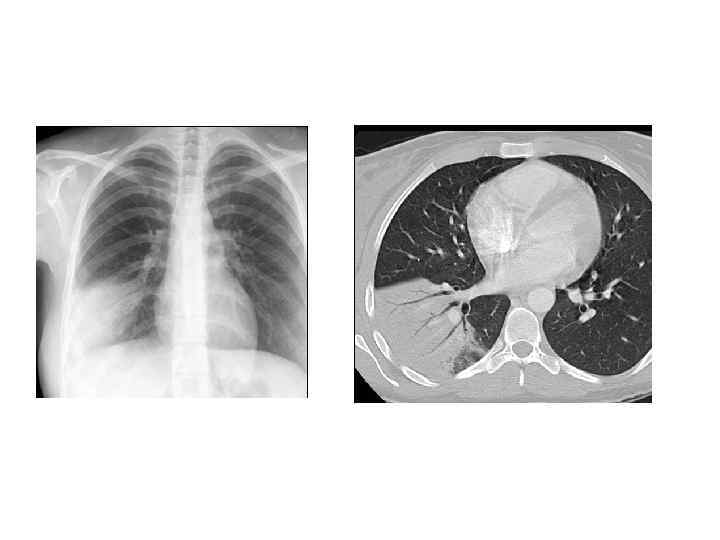

Рентгенологическая диагностика ВП • Рентген ОКГ является обязательным методом подтверждения диагноза пневмонии • Рентген ОКГ в двух проекциях должен быть проведен быстро при клиническом подозрении на пневмонию • Рентгенологический признак пневмонии – появление очаговой инфильтрации в легких

Показания к компьютерной томографии • При очевидной клинике ВП отсутствуют изменения в легких на рентгенограмме • Сложные диагностические ситуации • Затяжная пневмония (нет разрешения инфильтрата более 4 недель) • Рецидив пневмонии в той же доле